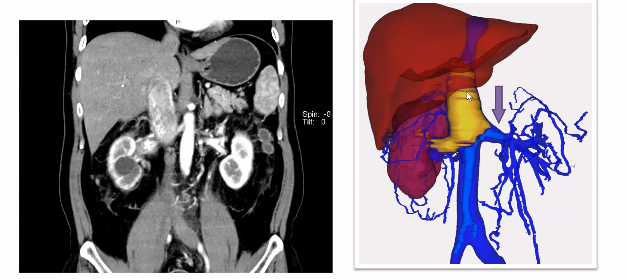

对于腔静脉各端及分支的充分游离和暴露是顺利取栓的重要条件,而各支血管的完全阻断更为关键。但是,下腔静脉一定要阻断吗?既往积累经验告诉我们瘤栓上方下腔静脉完全不用阻断。如下图所示,病例患者具有肾静脉和肾上腺中央静脉双瘤栓,在手术中取肾上腺中央静脉的瘤栓时,其上方腔静脉并没有阻断,而是通过剪开腔静脉直接将瘤栓取出。取栓之后,再把静脉壁切掉,可以获得足够空间后再重新进行阻断,有利于完成后续缝合等多个操作。(备注:视频中有动态手术操作过程)